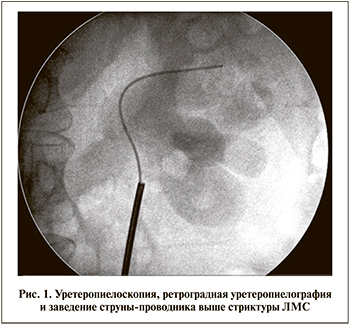

Спустя 6–8 нед. после операции интубирующие трубки удаляли. Контрольные обследования на основе оценки субъективных данных (наличия болей, дискомфорта в поясничной области на стороне операции), а также оценки объективных параметров (ультрасонографического и радиоизотопного исследований почек, в ряде случаев – экскреторной урографии и МСКТ) проводили через 8 нед., 6, 12 и 24 мес. после операции. Показателями, позволившими расценивать отдаленные результаты как положительные, считали отсутствие клинической симптоматики, снижение (отсутствие) пиелокаликоэктазии, отсутствие нарушения (улучшение) пассажа контрастного вещества по ВМП, улучшение функции почек.

В обеих группах отмечен положительный результат оперативного лечения (отсутствие клинической симптоматики), хорошая (удовлетворительная) проходимость ВМП; уменьшение пиелокаликоэктазии отмечено у 34 (94,4%) пациентов основной и 28 (96,5%) контрольной групп, улучшение функции почки по данным радиоизотопного исследования – у 26 (72,2%) и 26 (89,6%) соответственно (рис. 4). Рецидив стриктуры после проведенного оперативного лечения отмечен лишь у 2 (4,2%) пациентов основной группы и 1 (2,2%) контрольной. Всем выполнена повторная трансуретральная тулиевая эндопиелотомия.